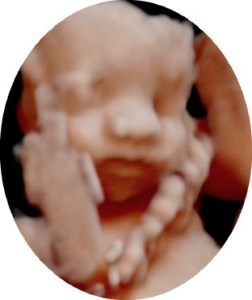

Terwijl alle kindjes bezoek krijgen van Sinterklaas, gaan papa en ik op bezoek bij Cfor9. Oma gaat mee, want ze is zo nieuwsgierig om haar kleindochter eens te zien.

Eerst verstop je je een beetje achter mama’s placenta, waardoor Sylvie geen mooie 3D-beelden kan maken, maar plots draai je je naar de andere kant. O, wat is het leuk om jou te zien en wat ben je al een knappe meid geworden! Volgens Sylvie lijk je op jouw papa en dit vindt papa natuurlijk leuk om te horen.

We genieten er echt van om jou te kunnen bewonderen!

Weet je wat meid… papa en ik zijn nu al trots op je!